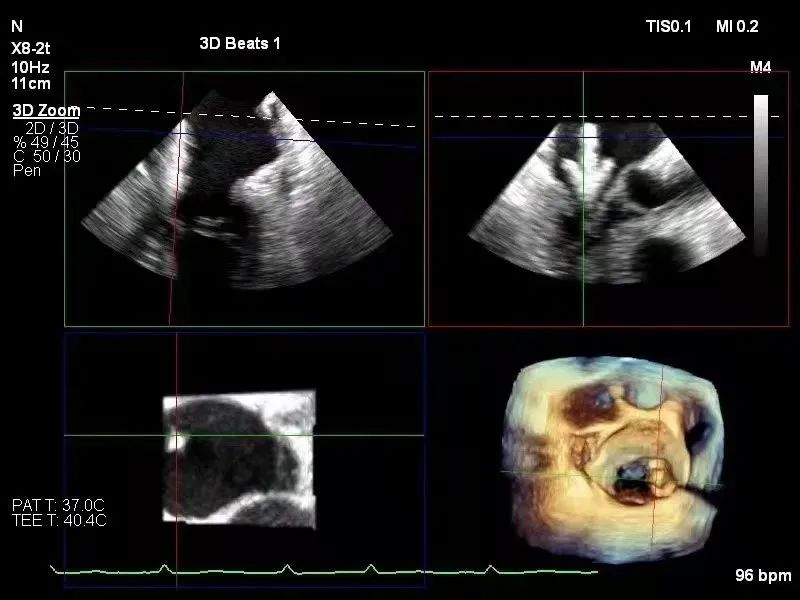

术者在食道超声和DSA引导下,通过反复评估二尖瓣脱垂范围、抓捕位置和角度,最终历时4.5小时仅用一枚宽夹子完成A3P3区域精准钳夹。

术中反复调整夹子的位置(3区)和方向(5-11点)

同时,浙江大学医学院附属第二医院王建安教授团队的刘先宝教授和蒲朝霞教授线上进行手术讨论。术后超声显示,术后二尖瓣反流显著减少,左房压力显著降低,血流动力学改善明显,手术取得圆满成功。